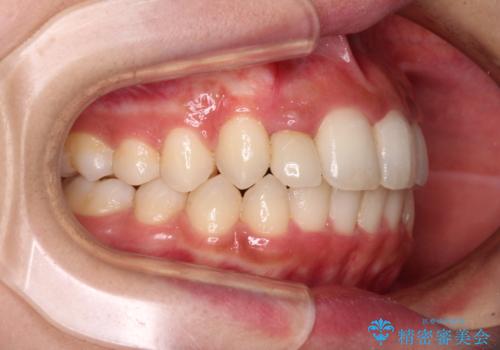

- 上下前歯のデコボコを気にして来院された患者様です。

前歯のセラミックが装着されている歯は、歯根が短くなっており、他院では抜けてしまうので矯正はできないと言われていたようです。

患者様と相談し、抜けてしまった場合にはインプラントあるいはブリッジによる補綴治療が必要となることを確認し、極力歯根に負担のかからないような仕上がりで治療を進めて行くこととしました。

デコボコを解消には、IPR(歯と歯の間を削る)をメインに歯列排列を設計し、インビザラインにて矯正治療を行うこととしました。

レントゲン写真上では、矯正治療前後で歯根長さに大きな違いはなく、抜歯を回避することができました。

上顎内側に転位している前から2番目の歯は移動が難しく、無理矢理歯根全体を動かそうと設計すると、歯肉退縮・歯髄壊死・歯根吸収といった危険性が増すため、無難なゴールにて治療を終えることとなりました。